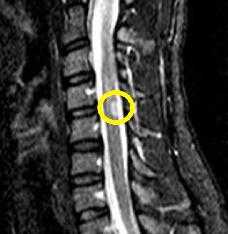

| Очаг демиелинизации в веществе спинного мозга |